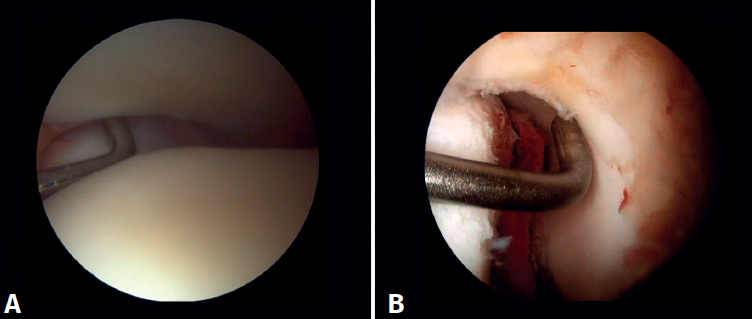

Surgical technique: arthroscopic treatment of acute syndesmosis injuries

The technique should be performed using the conventional anteromedial and anterolateral portals. The anteromedial portal is used for visualization, while the anterolateral portal serves as the working portal. Once the tibiofibular space is visualized, the inflamed synovial component is resected with an arthroscopic shaver to facilitate reduction (Figure 7A). Then, under direct vision, we restore the tibiofibular space, carefully taking into account possible malrotation of the fibula, especially in Maisonneuve type fractures. For fibular reduction we use a Verbrugge clamp, which allows us to correct the rotation. In our experience, once the space has been cleaned and if the position is correct, it is infrequent to have to use a compression clamp between the tibia and fibula.

Once the desired reduction has been achieved, we visually check the position and temporarily fix it using a Kirschner pin.

For definitive fixation, the surgical options range between rigid fixation with screws and dynamic fixation. Screws have been the standard procedure for decades, but involve complications, such as loosening or rupture. Furthermore, some surgeons advocate their removal, with the inherent risk of recurrence of instability(27). Dynamic fixation was designed to overcome some of these problems by allowing a degree of physiological movement of the syndesmosis, facilitating early weight bearing, reducing the risk of rupture, and eliminating the need to remove the implant (Figure 7B).

Grassi et al., in a meta-analysis involving over 300 patients, demonstrated an overall decrease in the relative risk of complications (RR = 0.55, p = 0.003) with dynamic systems(28). Raeder et al., in a randomized trial of 97 patients contrasting screw fixation versus a dynamic system, reported a lower incidence of osteoarthritis with suture buttons of 65% versus 35% (p = 0.009) at 5 years(29). Suture button constructions afford a degree of micro-mobility, mimicking physiological mobility, which can promote ligament healing. Likewise, flexible implants are better able to tolerate an imperfect reduction, as a possible complication, even if arthroscopic control of the joint is performed.